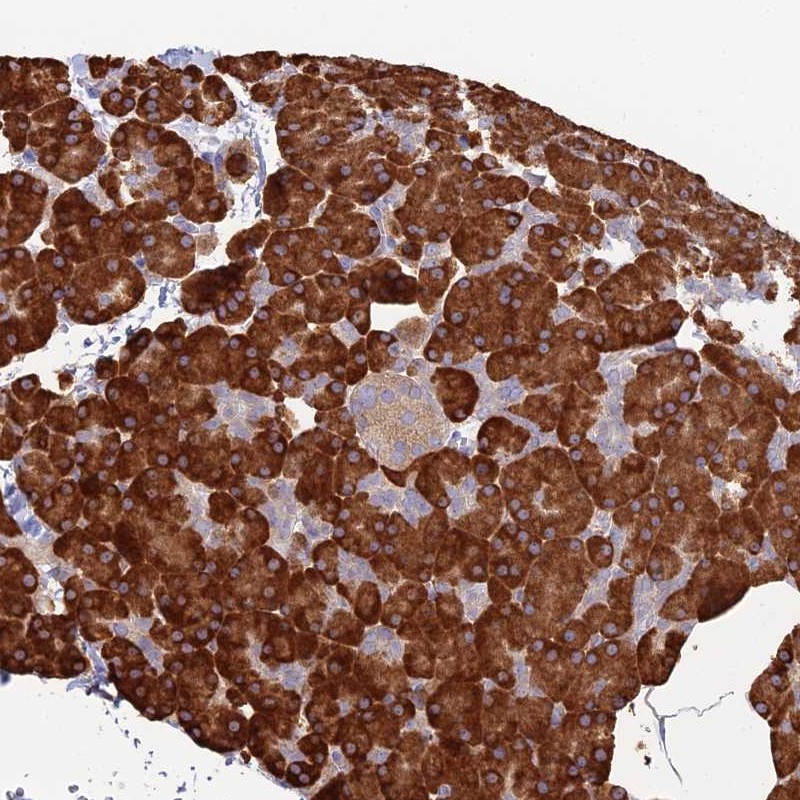

Immunohistochemical staining of human pancreas shows strong cytoplasmic positivity in exocrine glandular cells.